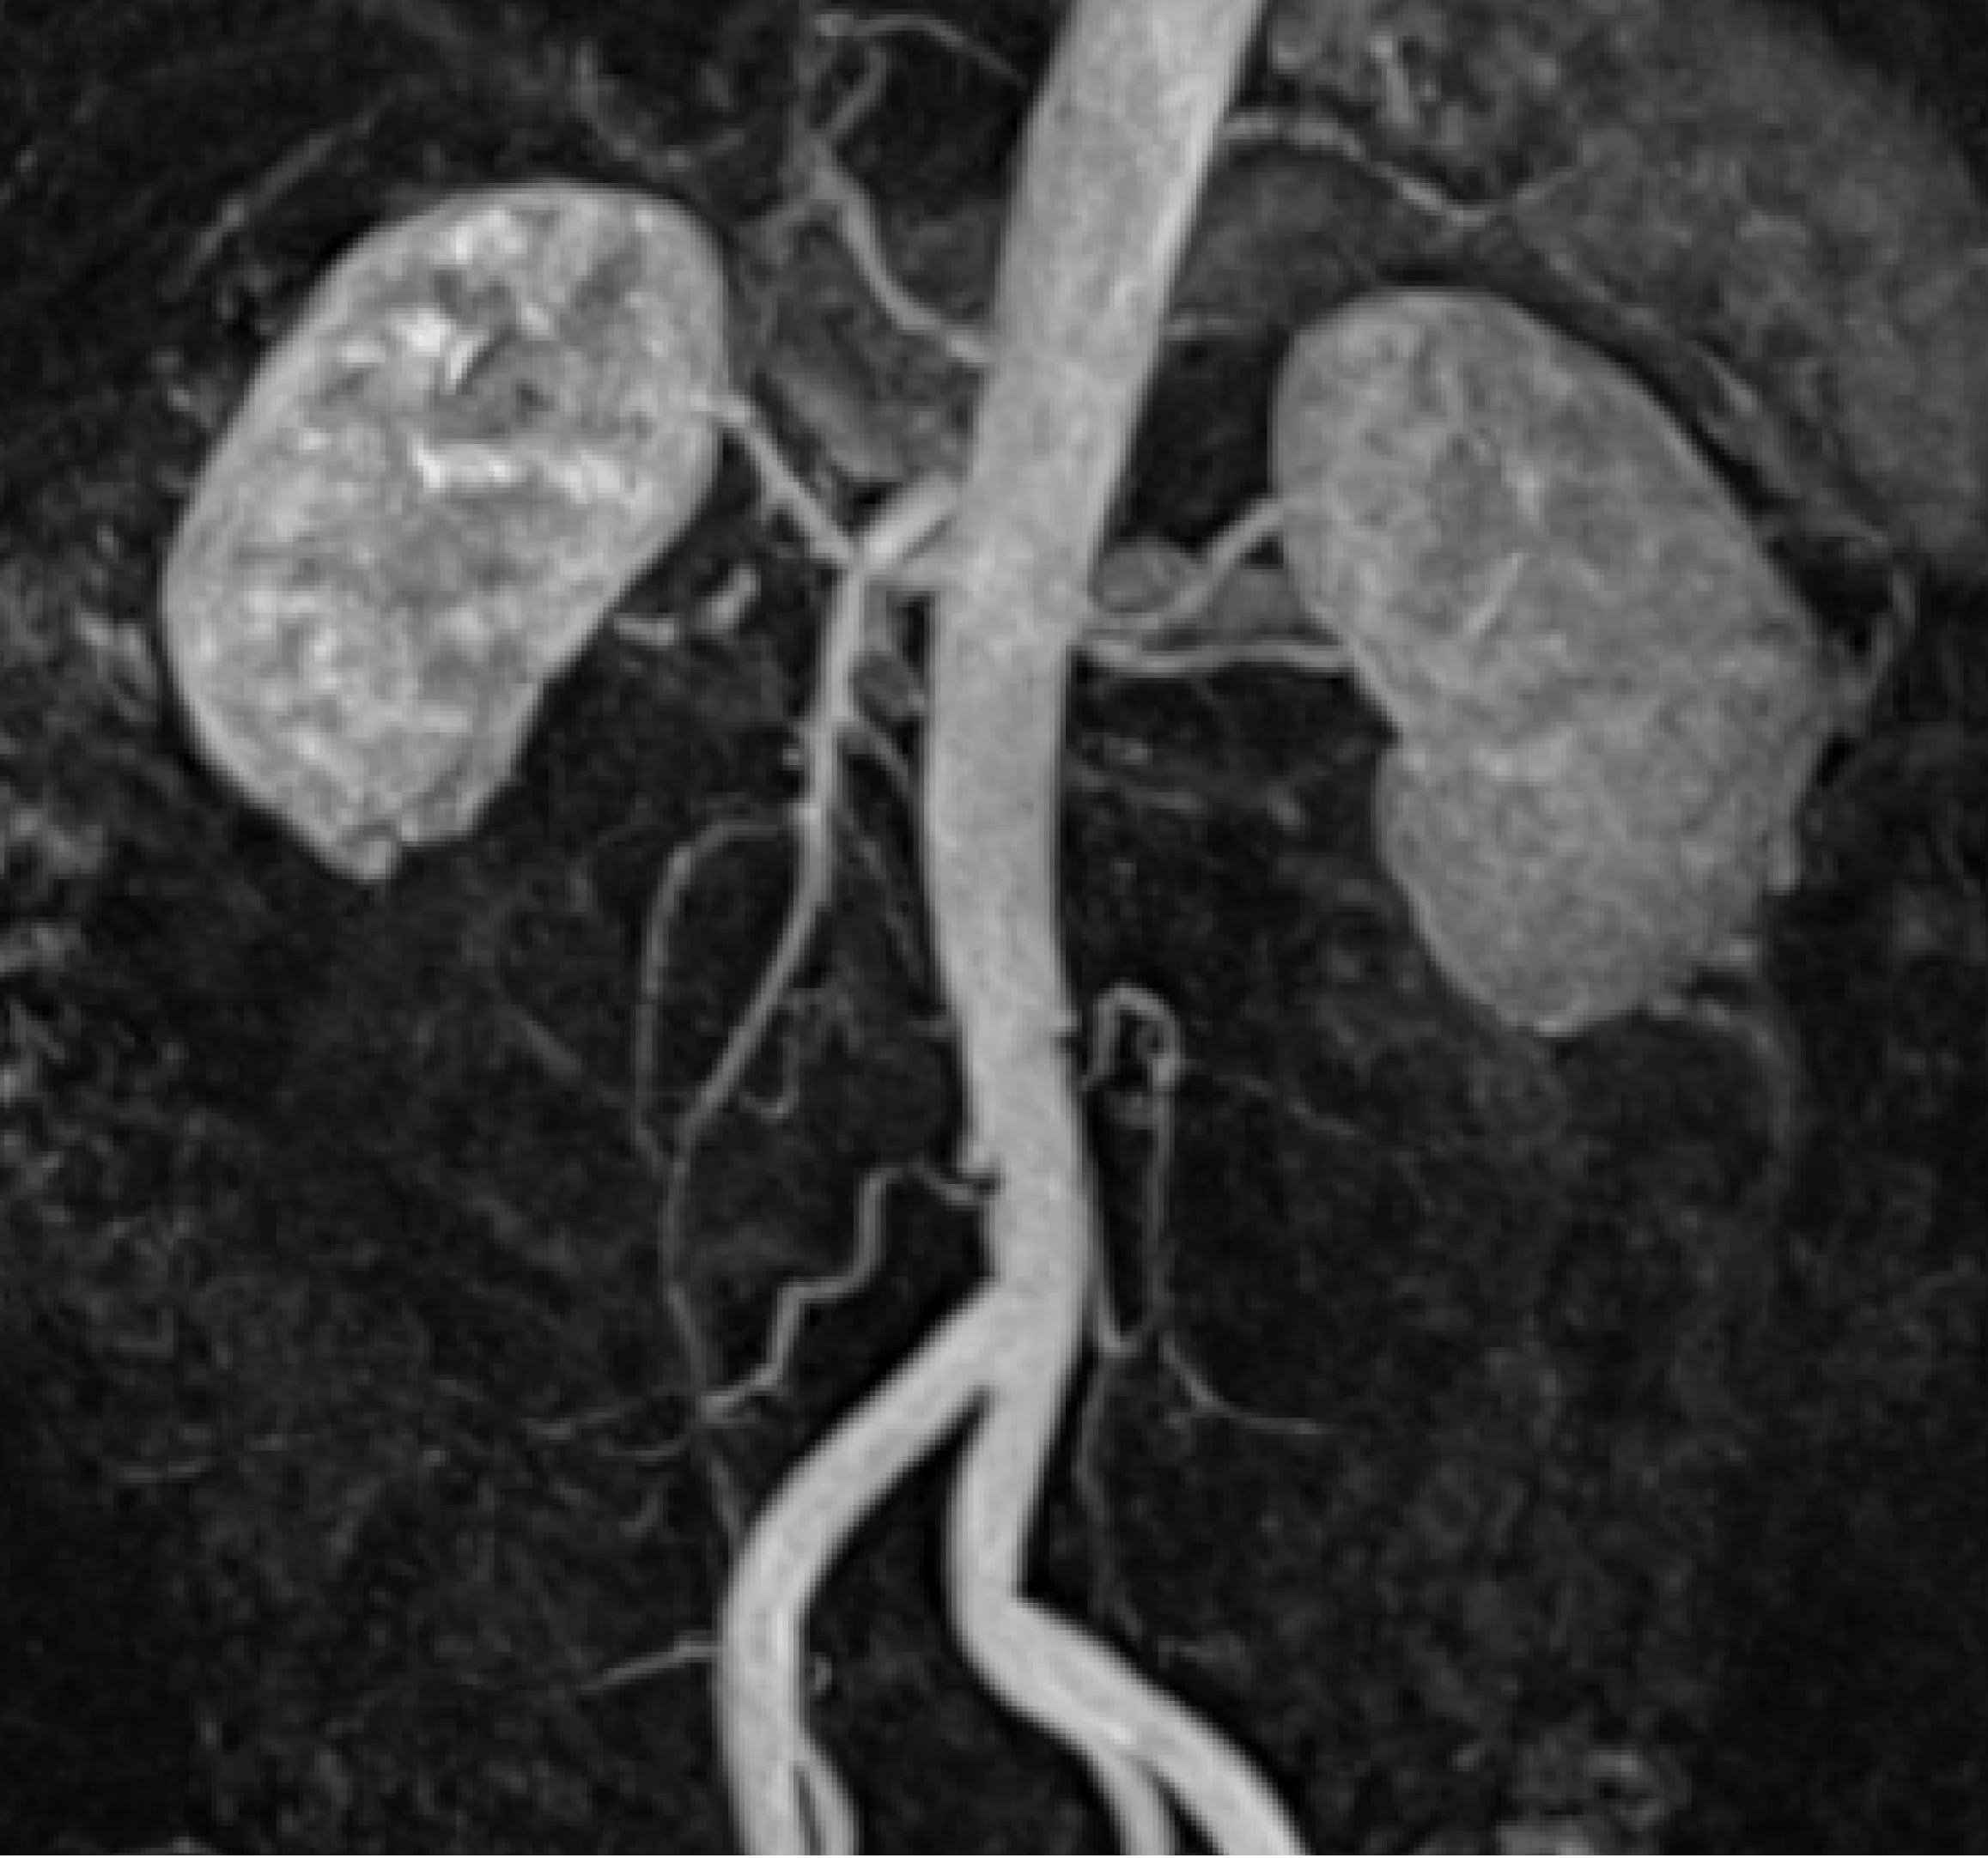

2. Case Presentation